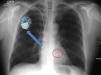

Figura 5.Marcapasos ventricular en modo unipolar. Se observa estímulo del dispositivo previo al QRS (ritmo de estimulación ventricular). Dado que no hay un cable auricular, no se preserva la sincronía AV, lo que se observa como ausencia de relación entre las ondas P (flechas azules) y los complejos ventriculares. En el modo VVI, la presencia de QRS intrínseco inhibe al marcapasos.